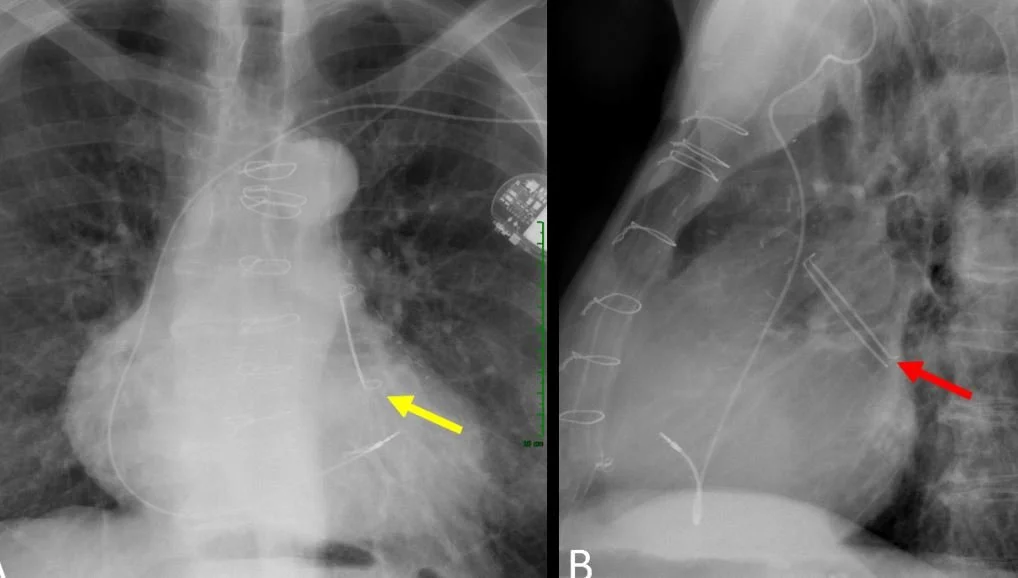

A 58 y.o. male sp ablation for a fib x 2 comes to the ED with L arm and L leg weakness

all that can be seen on cxr is the central knob of the WATCHMAN

during placement the intra atrial septum must be punctured to place the device.

LEFT ATRIAL APPENDAGE CLOSURE

Currently another procedure can be offered; occlusion of the L atrial appendage. This is where most clots form and by occluding the opening they cannot escape into the aorta to cause stroke.  The procedure is called WATCHMAN or amulet and can be done through the femoral vein  . After implantation a TEE is performed to confirm  placement and closure of the left atrial appendage.